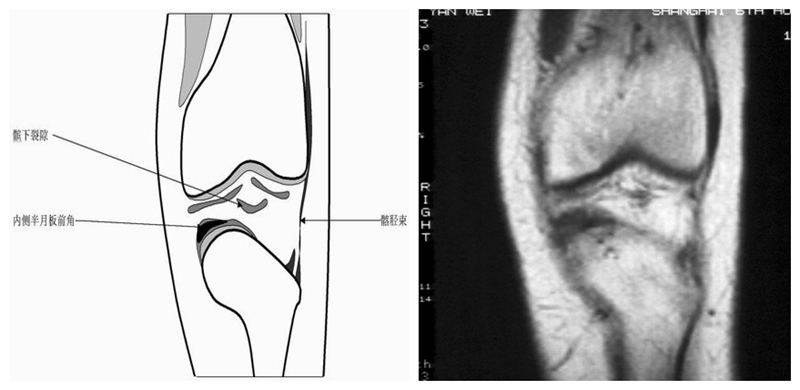

膝关节冠状面MRI解剖

显示内外侧副韧带、腘肌和拱状韧带,有无信号和结构改变,侧重关节胫股软骨的两边和半月板的体部。

冠状位解剖第一层

冠状位解剖第二层